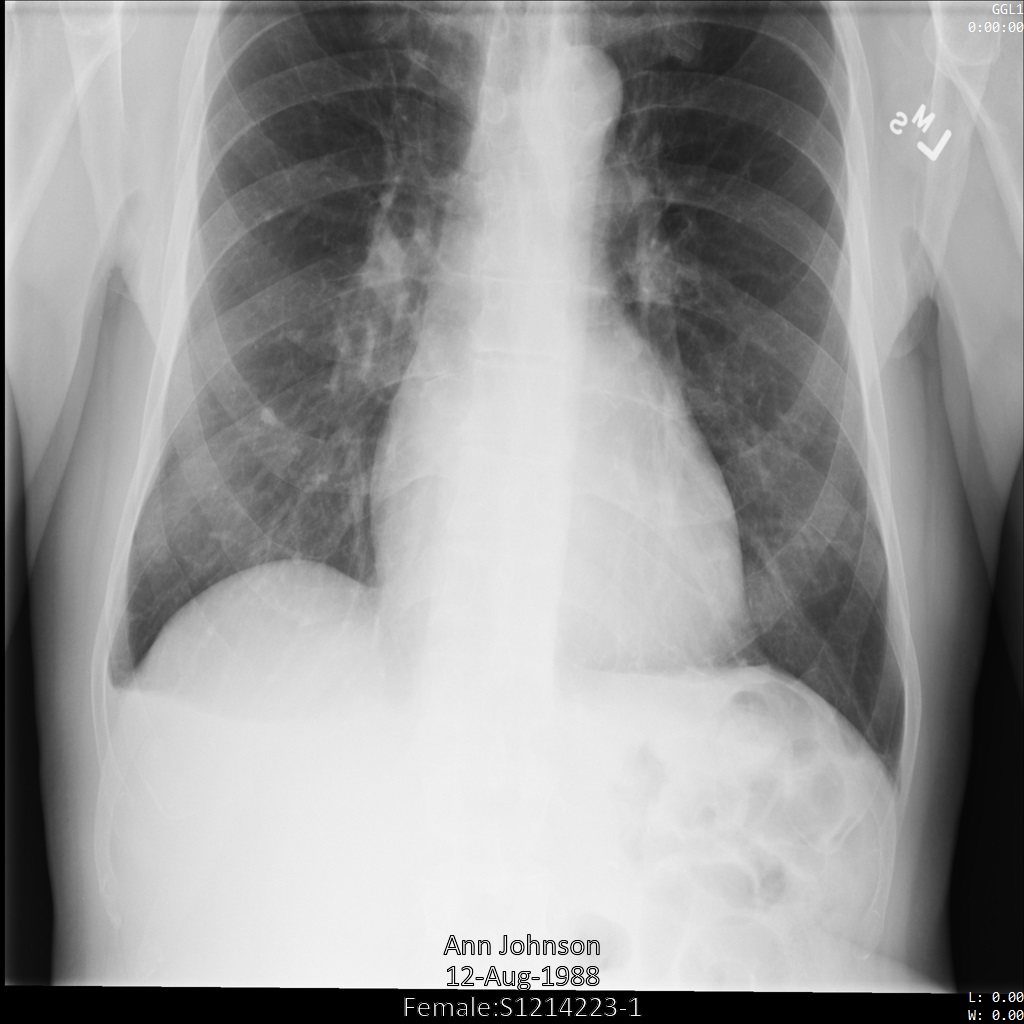

以下各部分提供的示例展示了如何使用各种方法对 DICOM 数据进行去标识化。每个示例都会提供去标识化后的图片输出。每个示例都使用以下原始图片作为其输入:

您可以将每个去标识化操作的输出图片与该原始图片进行比较,以查看该操作的效果。

将图片提交到 Cloud Healthcare API 后,图片显示如下。虽然图片顶部角落显示的元数据已被遮盖,但图片底部的烧屏受保护健康信息 (PHI) 仍然保留。如需一并移除烧屏文字,请参阅遮盖图片中的烧屏文字。